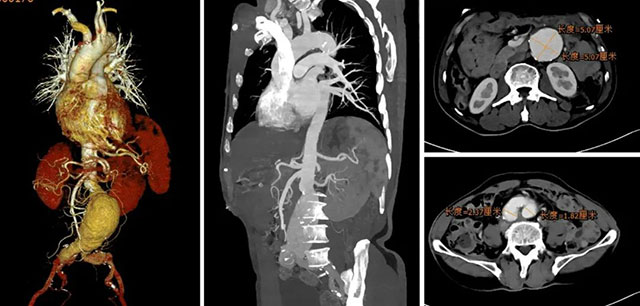

入院后,值班医生迅速完善了相关辅助检查,主动脉CTA提示:腹主动脉下段及双侧髂总动脉瘤形成,腹主动脉瘤大小约107mm*61mm*52mm;左侧髂总动脉瘤大小约21mm* 36mm;右侧髂总动脉瘤大小约37mm*44mm。

术前影像